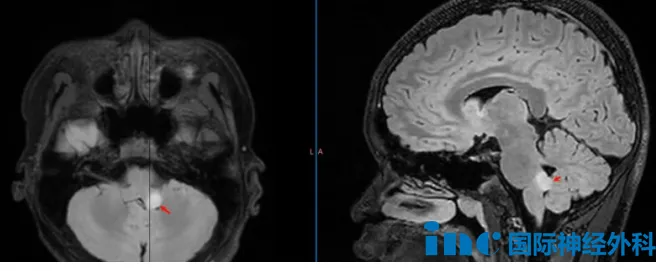

嘉乐确诊该严重病变已2年。初期仅表现为普通头痛头晕——这是儿科疾病中常见症状,但其背后病因多样,对应疾病严重程度各异。常见原因包括呼吸道感染或胃肠道疾病;严重情况可能涉及颅内疾病。对嘉乐而言,首次检查发现:左侧桥臂存在8毫米结节。

11月复查结果令所有人震惊:病灶在半年内几乎增长一倍,达到13×13×10毫米。"建议手术。"此次医生提出不同建议,但该位置手术风险较高。

巴教授评估嘉乐情况:从5月至11月,短短半年病变体积近乎翻倍。若再等待半年,很可能再次倍增,情况将更复杂。而且,过去半年病变快速增长,本身提示肿瘤内部可能发生改变,这种变化甚至可能导向恶性转化。不仅是体积问题,肿瘤侵袭性才是关键。